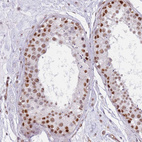

Immunohistochemical staining of human colon shows moderate cytoplasmic and nuclear positivity in glandular cells.